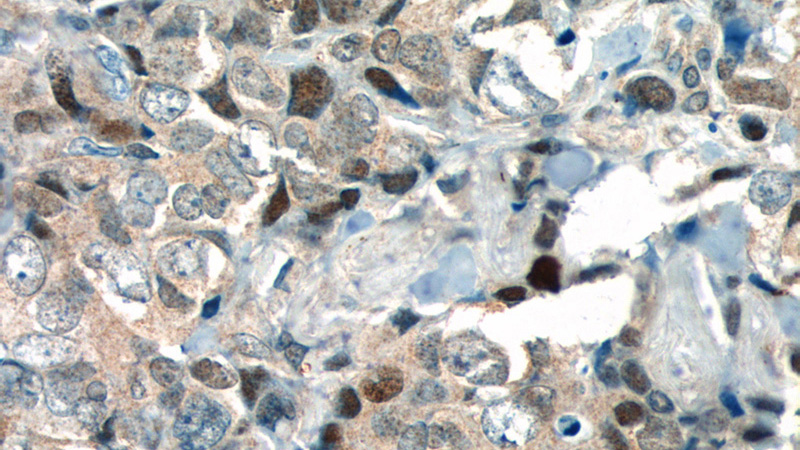

Immunohistochemistry of paraffin-embedded human breast cancer tissue slide using Catalog No:112041(KI67 Antibody) at dilution of 1:400 (under 40x lens). heat mediated antigen retrieved with Sodium Citrate buffer (pH6).